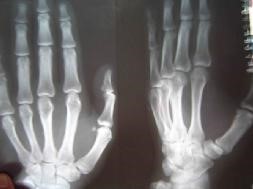

此前,二零零二年五月二十八日,邢家秋在钢屯镇虹螺山发真相,被当地派出所绑架,遭到钢屯恶警昼夜酷刑折磨后,被投入葫芦岛市看守所。七月被非法秘密判刑六年,九月被投入沈阳第三监狱(沈阳监狱城)迫害。二零零三年大年过后,邢家秋遭强制“转化”,恶警指使犯人王权强制他面壁罚站,每天被迫面壁而立十二小时,稍有不从就会招来一顿毒打。他的腿严重受伤,不能正常走路。

二零零三年三月,邢家秋不堪残酷的摧残,以绝食抗议。在监区队长王晓波、董仑山的指使下,犯人王权、李素安等人在操作间里对他进行围殴。李素安找来一根铁锹把儿,犯人们把他摁倒在地,扒下他的棉裤,分别踩着、摁着他的头、腿、胳膊,李素安抡起锹把猛烈抽打他的腰、臀等部位。因为剧痛,邢家秋用手去挡,手却被李素安抡了一棒,他晕了过去,这时,他的手背肿得像个馒头,不能动。第二天,李素安、金永军对他又一顿毒打,李素安冲着他受伤的手砍了一掌,他痛得坐在地上,此后他的手剧烈疼痛不敢动。

二零零五年六月在沈阳第一监狱拍的X光片子显示邢家秋左手中指骨折